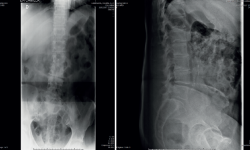

Figura 3. Radiografía a los 3 meses del ingreso inicial.

La analítica se había normalizado. En la radiografía lumbar (Figura 3) se veían signos de discopatía grave.